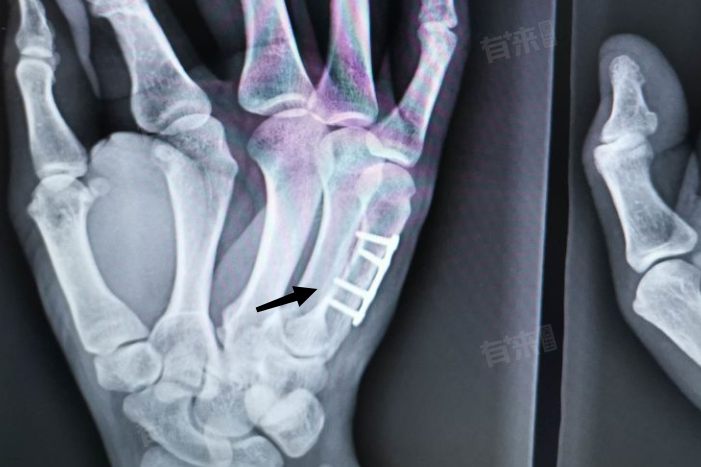

- 如果保守治疗效果不佳,骨折断端存在明显的间隙或硬化,可能需要进行手术治疗。手术方法包括植骨术,即从患者自身的髂骨、腓骨等部位取骨,移植到骨折不愈合部位,提供新的成骨细胞和生长因子。还可以采用内固定或外固定装置的调整,重新稳定骨折断端。对于严重的骨不连,如伴有感染、骨缺损较大的情况,可能需要更为复杂的手术,如带血管蒂的骨移植、骨搬运技术等。